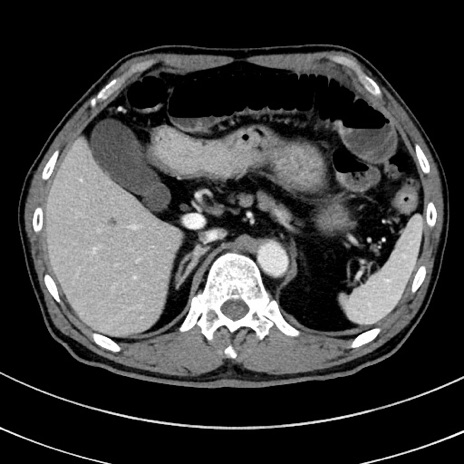

症例8(横断像)

【症例】 60歳代男性

【主訴】 黒色吐物

【現病歴】 4日前から嘔気自覚、2日前の朝食後にも嘔気あり、自分で手で嘔吐反射起こし嘔吐したところ血が混ざっていたため受診。

【既往歴】 5年前汎発性腹膜炎を伴う急性虫垂炎で手術、高血圧、前立腺肥大症、高脂血症

【身体所見】 腹部正中に手術癩痕あり 腹部平坦・軟圧痛なし膨満感あり

【データ】WBC 8400、CRP 4.54